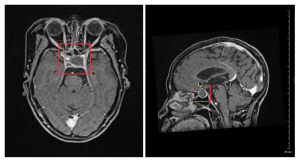

Khoa Phẫu thuật thần kinh – Cột sống, Bệnh viện Đa khoa (BVĐK) Thái Bình